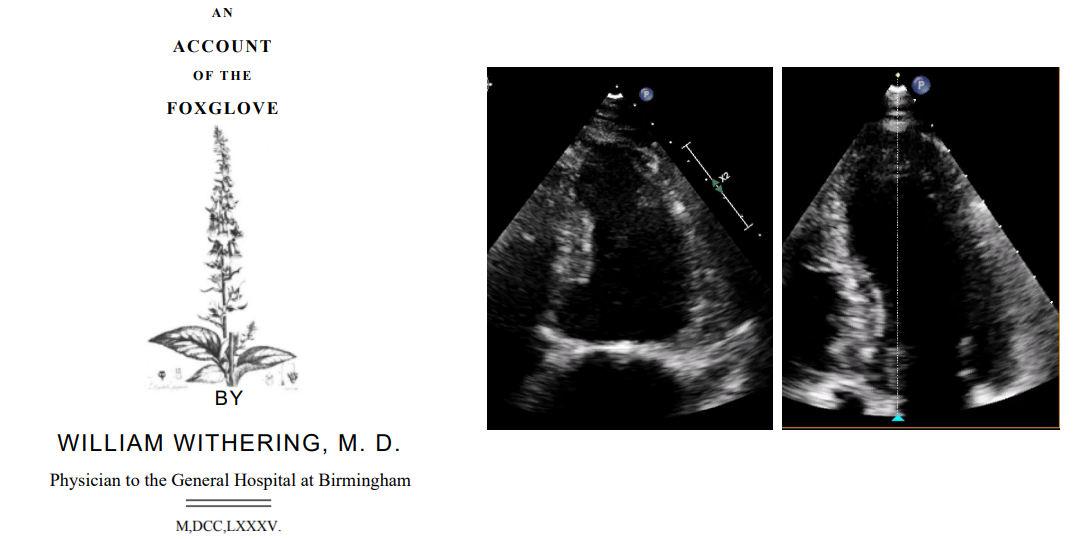

洋地黄类药物地高辛治疗心力衰竭已有200多年的历史。18世纪晚期英国伯明翰医院威廉·威瑟林医生描述了其药理作用,后来地高辛被广泛应用于心衰和心房颤动等治疗(图1)。由于受到较高死亡率报道的影响,导致其临床应用受到限制。考虑到观察性研究和回顾性研究的限制性,本项系统综述旨在全面客观地分析地高辛治疗的安全性和有效性。